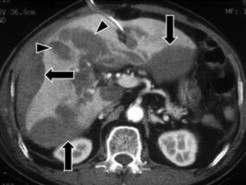

- Đụng dập nhu mô: vùng nhu mô gan bị đụng dập thường giảm tỷ trọng không đều trước khi tiêm thuốc cản quang, sau khi tiêm bắt thuốc cản quang kém và không đều. Kích thước vùng đụng dập rất thay đổi có thể là một vùng giới hạn hoặc lan rộng chiếm một vùng của tạng bị chấn thương [21].

Hình 1.8: Rách gan và đụng dập – tụ máu nhu mô (mũi tên ngắn) vùng không có phúc mạc phủ gây tụ máu sau phúc mạc (mũi tên dài).

Nguồn: Shanmuganathan K, Mirvis SE [21].